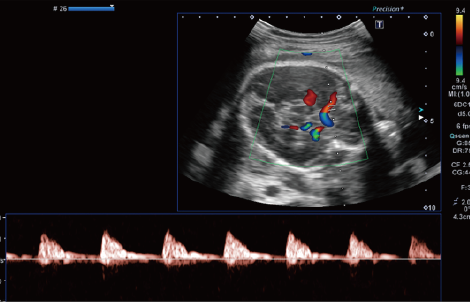

産婦人科産婦人科

• 胎児 頭部内血流